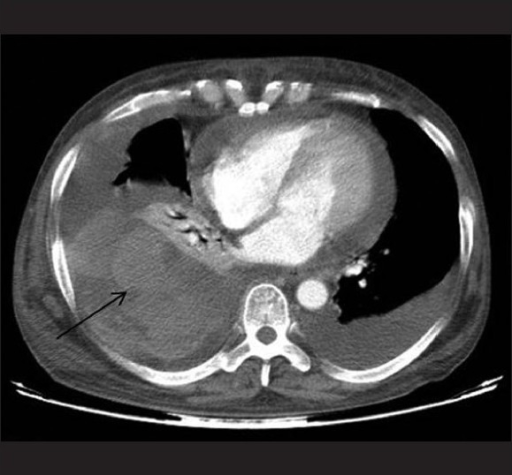

- Chest X-ray – can be used to image any problems or abnormality in lung pathology (e.g. pleural effusions etc).

- Computed Topography – can be used for an intensive and more detailed imaging of injuries and abnormalities in the anatomical pathology (e.g. detection of pulmonary emboli or airway tumor).